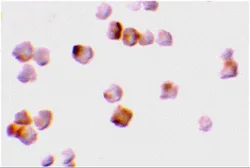

Description Rabbit PolyclonalApplications WB ICC/IF ELISAReactivity Hu, MsSummary Depending on cell lines or tissues used, other cleavage products may be observed.

Description Rabbit PolyclonalApplications WB IHC-P IPReactivity Hu, Ms, Rat

Summary React with caspase-2L p12 subunit and precursor (also designated Ich-1L).